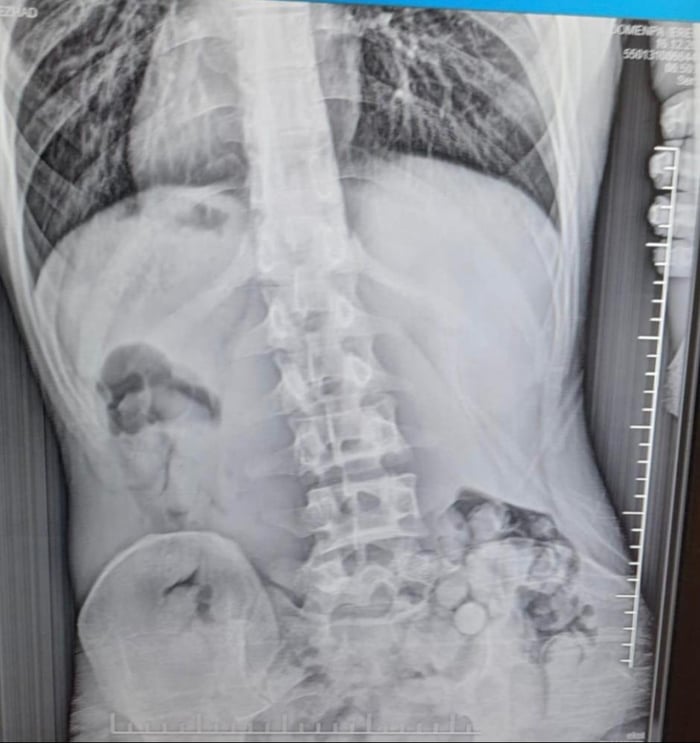

Samsun'un Çarşamba ilçesinde, bağırsağında 51 uyuşturucu kapsülü ele geçirilen İran uyruklu şahıs gözaltına alındı.